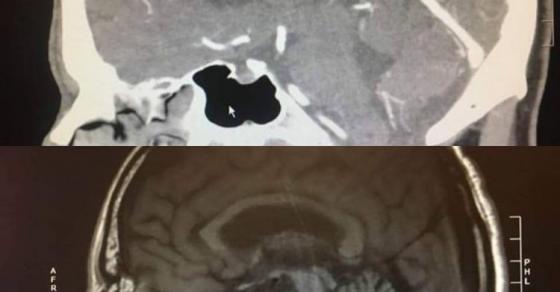

Hình ảnh não ông Paul khi mới phát hiện khối u và trước thời điểm dự định phẫu thuật 1 ngày.

Trời đất như sụp đổ trước mắt ông Paul khi bác sĩ giải phẫu thần kinh tại bệnh viện UC San Francisco thông báo một tin sét đánh rằng ông đã bị chảy máu não. Rồi kết quả chụp X-quang lại cho thấy ông Paul có một khối u trong não. Cả 2 kết quả đều không phải là tin tốt lành đối với Paul vì ông buộc phải làm phẫu thuật gấp để tránh nguy hiểm đến tính mạng và để lại hậu họa về sau.

Thế rồi, trước ngày lên bàn mổ 1 ngày, ông Paul đến bệnh viện để chụp cắt lớp lần nữa thì bác sĩ phát hiện ra khối u đã tự nhiên biến mất, não của Paul hoàn toàn bình thường. Trong khi các bác sĩ bối rối không hiểu chuyện gì đang xảy ra với người đàn ông này thì ông Paul cho rằng đó là phước lành mà Chúa đã ban cho ông. Paul coi đó là điều kỳ diệu.

Sau đó bác sĩ đề nghị Paul hợp tác để tiếp tục nghiên cứu xem tại sao lại có chuyện hoang đường như vậy xảy ra. Tấm phim chụp vẫn còn đó, đốm trắng trong não Paul là hoàn toàn có thật nhưng không ai hiểu tại sao nó lại biến mất bí ẩn như vậy.